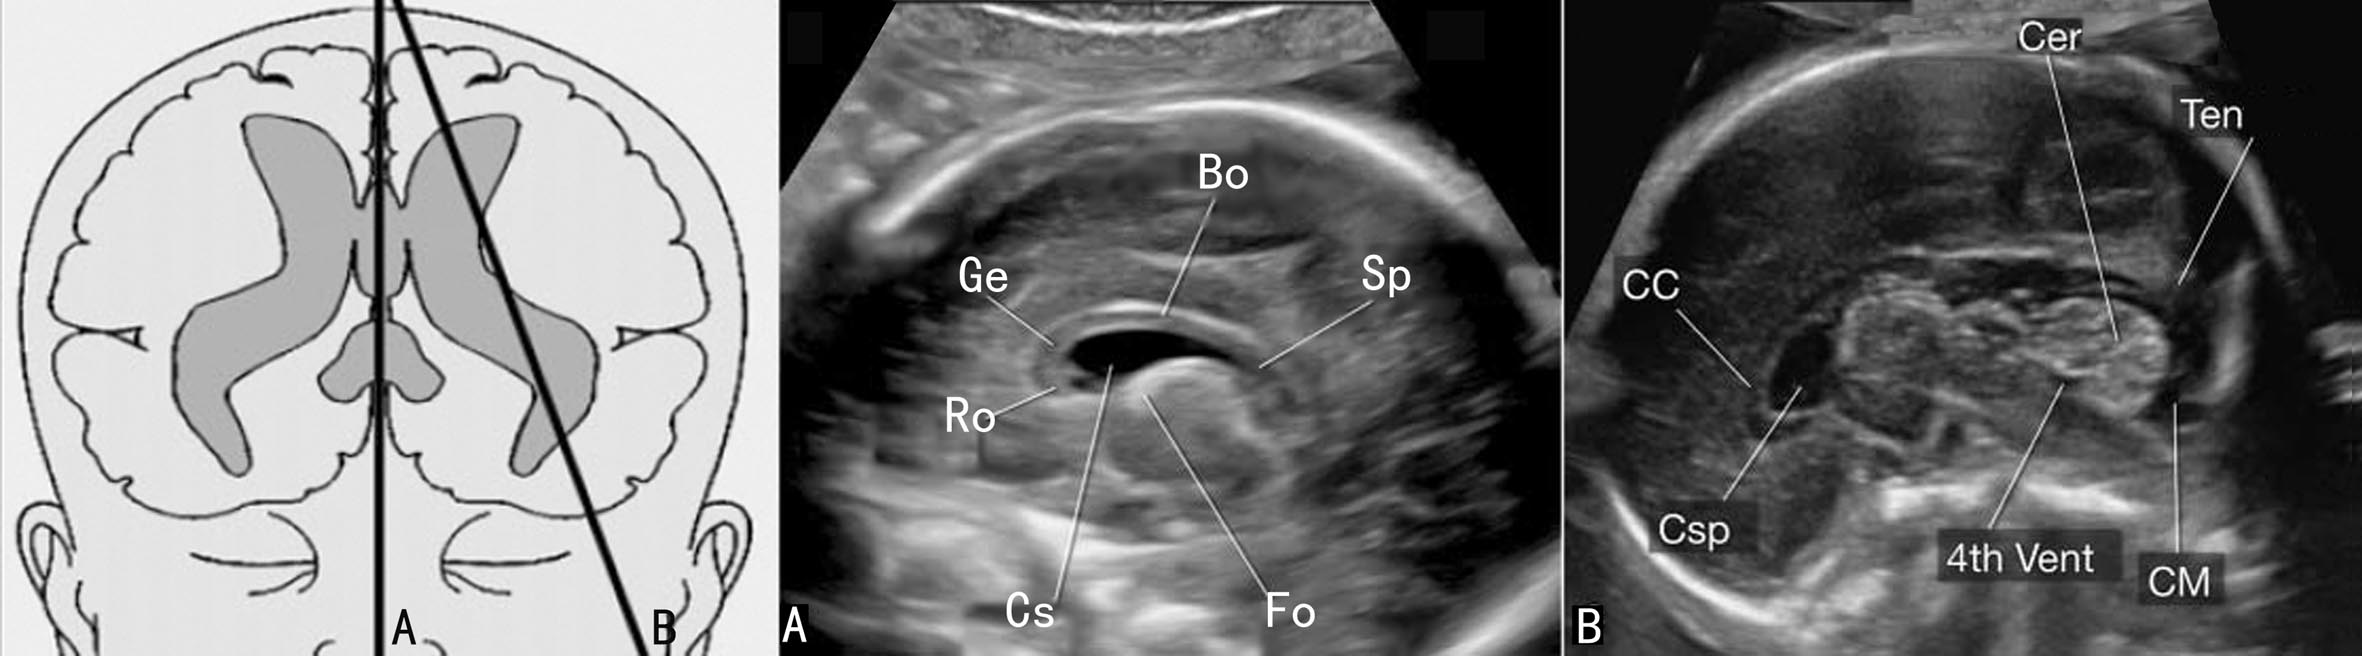

二、冠状面

胎头的冠状面(CP)结构辨认相对困难,在头位时TVU相对容易显示;臀位时或其他胎位时,如果胎头额顶部贴近母体腹侧,则TAU适当调整探头可以显示胎头的冠状切面。

探头与胎儿面部平面平行、由前向后可以显示胎儿头部一系列CP。前额CP显示的结构主要包括中部由大脑纵列形成的强回声及其两侧均匀的大脑额叶,颅顶及侧部显示膨隆的颅骨强回声,颅底两侧稍向颅内对称的膨起由眶腔顶部形成(图7-4A);探头稍向后倾斜可在脑实质中部近大脑纵裂区域显示TV前角,大脑纵裂强回声的上端的三角形无回声为上矢状窦,下部终止于SP的菱形回声上方的胼胝体部膝部,后者显示为连接大脑半球的中等回声;脑实质内由于脑裂和沟回的出现而形成不同的区域和不均匀的回声(图7-4B);偏外下方可见大脑侧裂回声。

探头向后移动近中部CP时可以显示丘脑平面,上述结构仍可见显示,TV体部显示较小,周围的脑实质回声不甚均匀,SP深部的稍强回声为丘脑,大脑侧裂显示更为明显(图10-4C),位于深部中线区域、丘脑稍前方的回声包含颅底动脉环及视交叉等结构;在探头移动过程中有时还可显示第三脑室。探头继续后移显示小脑时称为经小脑平面或枕部平面。比较明显的结构就是TV后角、CP、小脑和小脑蚓部、CM等(图7-4D)。

图7-4胎头冠状面声像图

(三)胎儿颅脑矢状面

胎头矢状面包括正中矢状面(MSP)和正中旁矢状面(PMSP)。

1. MSP 探头切面选择胎儿头部正中可以获得胎头MSP,显示胎头横切面不易完全显示的胼胝体和CSP。MSP显示胼胝体位于图像中部,呈月牙形低回声或两条平行的带状稍强回声(图7-5),前方偏下方为喙部,向前突出的为膝部,中段为体部,后方为压部。在孕12周时从胼胝体头侧开始发育,至19周左右胼胝体完全形成,胼胝体上方为扣带回,越靠近妊娠足月时,扣带回越明显。腹侧包绕的无回声区为CSP。理想的图像还可以在后部显示第三脑室、第四脑室、小脑蚓部及CM等结构(图7-5)。

2. PMSP 显示MSP后将探头向旁边倾斜可以获得PMSP(图7-5B)。在此切面上颅骨强回声内的脑组织为大脑半球,其内部的TV显示为“C”形无回声,开口朝向面部,内部大部分由脉络膜的强回声占据;TV包绕的低回声为丘脑,侧动探头可显示TV前角、体部、后角。

图7-5胎头矢状面声像图